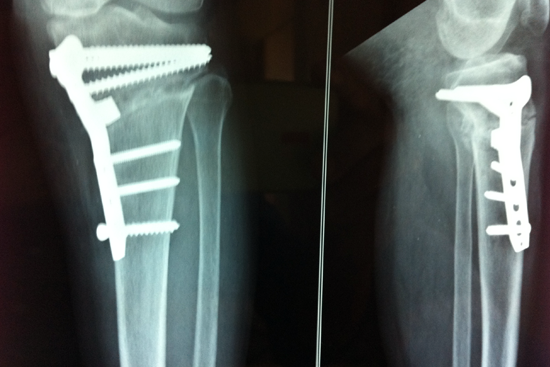

HTO

Rameshwar

Rashilaben

Shantaben